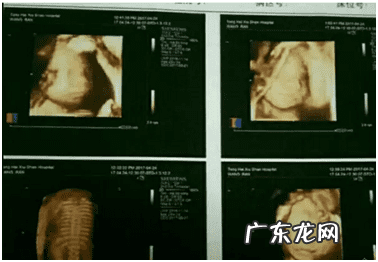

B超检查:

孕中期以后,通过B超可大致辨出胎儿的性别,但这跟胎儿当时的体位、B超医生的专业水平和经验有关,医生是禁止告诉孕妇或家属胎儿性别的 。